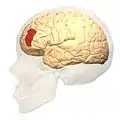

Brodmann area 46, or BA46, is part of the frontal cortex in the human brain. It is between BA10 and BA45.

BA46 is known as middle frontal area 46. In the human brain it occupies approximately the middle third of the middle frontal gyrus and the most rostral portion of the inferior frontal gyrus. Brodmann area 46 roughly corresponds with the dorsolateral prefrontal cortex (DLPFC), although the borders of area 46 are based on cytoarchitecture rather than function. The DLPFC also encompasses part of granular frontal area 9, directly adjacent on the dorsal surface of the cortex.

Cytoarchitecturally, BA46 is bounded dorsally by the granular frontal area 9, rostroventrally by the frontopolar area 10 and caudally by the triangular area 45 (Brodmann-1909). There is some discrepancy between the extent of BA8 (Brodmann-1905) and the same area as described by Walker (1940).[1]